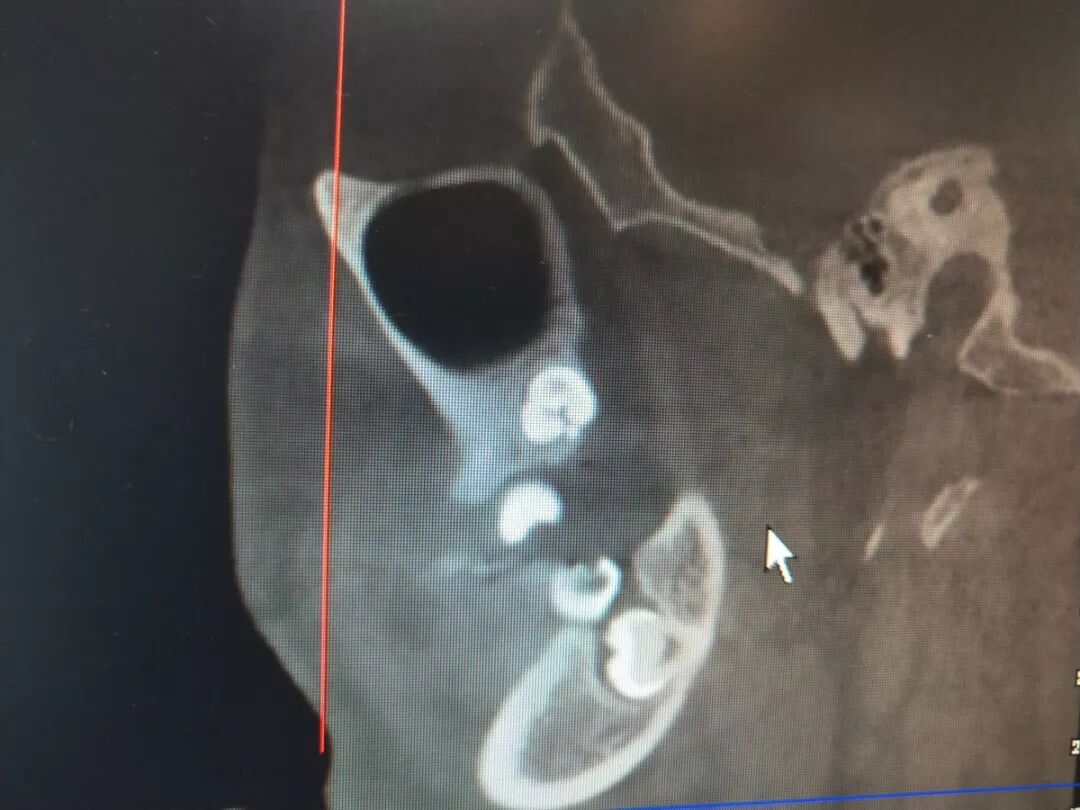

(CBCT的矢状面截图显示:整个牙体完全与下颌管紧贴)

考虑到小昕工作繁忙,无法腾出时间住院拔牙,经过详细的检查,并与科室专家进行了科学论证,王医生在神经阻滞麻醉下切开了小昕的牙龈,干净利落地使用工具磨去了智齿的牙冠部分,并顶出牙根,过程中修整了部分骨头,清理了牙槽窝,最后复位缝合牙龈。